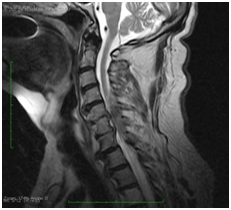

After the thrombolytic therapy, his NIHSS was noted to be 7 and there was evidence of partial recovery of strength in the right upper extremity. At the same time, he reported new interscapular pain radiating to the cervical region. Considering the persistence of pain, despite the mild but gradual neurologic improvement, magnetic resonance imaging of the cervical and thoracic spine was obtained. MRI revealed a posterior epidural intraspinal lesion extending from C4 through C7, along the dorsolateral aspect of the spinal canal and toward the right side, compatible with diagnosis of SEH (Figures 1-4). Decompressive laminectomy was then performed resulting in progressive recovery of the neurologic deficits (strength grade IV in both right upper and lower limb in the outpatient follow up).

Figure 1 Sagittal T2 weighted image MR through cervical spine shows a heterogeneously hypointense dorsal epidural lentiform shaped lesion, between C4 to C7 levels causing cord compression and edema.

Figure 2 Sagittal T2 weighted image MR through cervical spine shows a heterogeneously hypointense dorsal epidural lentiform shaped lesion, between C4 to C7 levels causing cord compression.